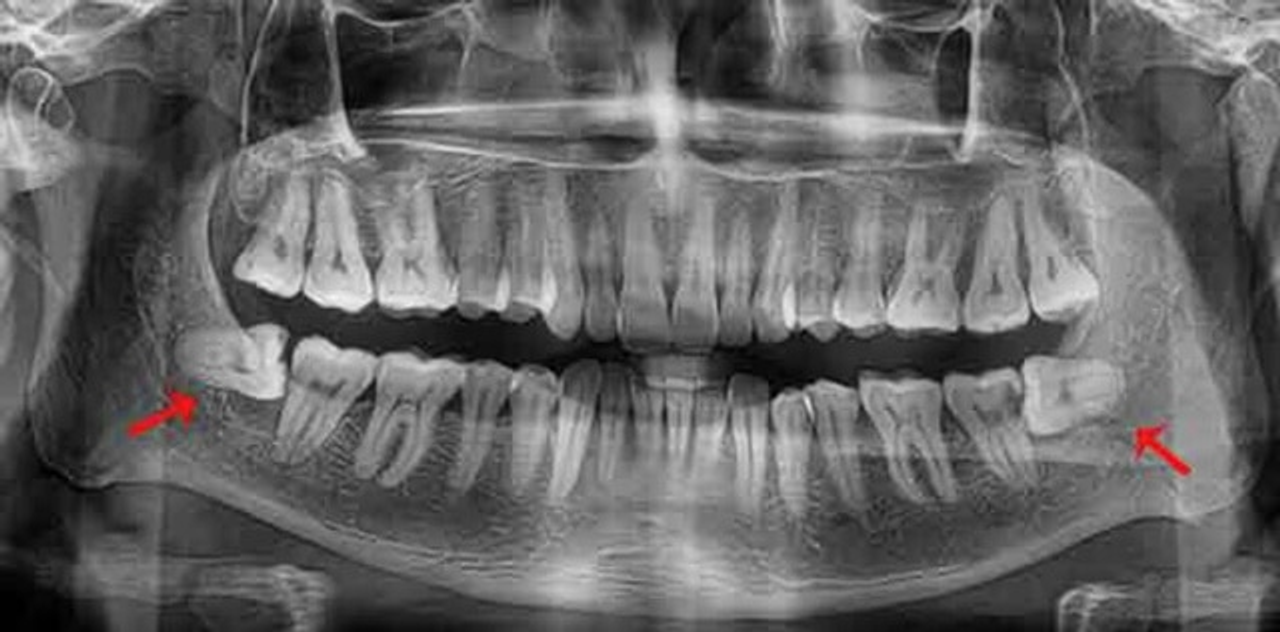

Vậy nên, bạn hãy đi nha khoa kiểm tra răng. Nhiều phòng khám bác sĩ có khám miễn phí bằng mắt thường luôn í, đừng ngại. Còn nếu muốn biết rõ hơn thì sẽ chụp X Quang khung răng để bác xem cấu trúc hàm và chân răng sẽ chính xác hơn. Để nếu có vấn đề gì, hãy hành động sớm để bảo vệ răng nhé. Luôn là phòng bệnh hơn chữa bệnh mà.

X quang nó kiểu vầy nè